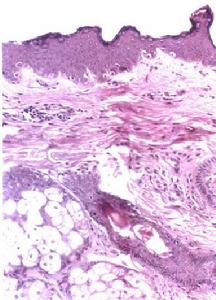

2.據Kesler等報導腫脹的唇部組織病理檢查證實為非特異性棘皮症及上皮下慢性炎症屬肉芽腫性質疑及本病是某些病原體感染所致

唇舌水腫及面癱綜合症2.檢查時除周圍性面神經麻痹及口唇腫脹外常可見舌面腫起或有較深縱向裂溝的舌體。這種舌面裂溝為本綜合徵的特徵性表現。